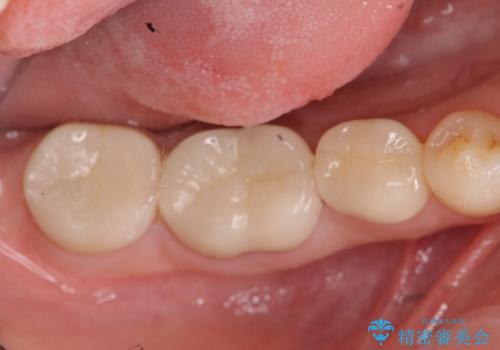

歯冠長延長術・骨隆起除去を行った、スペースの少ないセラミック治療

治療途中で長期間放置していたため、歯が歯ぐきから挺出(伸びてくる)してしまい、十分に強度を担保できるセラミッククラウンを装着するスペースが不足した状態です。

加えて、舌の邪魔になっている骨隆起や根尖病変といった問題を歯周外科・精密根管治療を行い、しっかりとスペースを確保したのちセラミッククラウンを作製していきます。